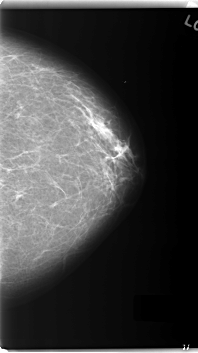

C_0163_1.LEFT_MLO

LEFT_MLO LINES 5968 PIXELS_PER_LINE 3464 BITS_PER_PIXEL 12 RESOLUTION 50 OVERLAY

FILE: C_0163_1.LEFT_MLO.OVERLAY

LESION_TYPE MASS SHAPE OVAL MARGINS MICROLOBULATED

ASSESSMENT 5

SUBTLETY 5

PATHOLOGY MALIGNANT